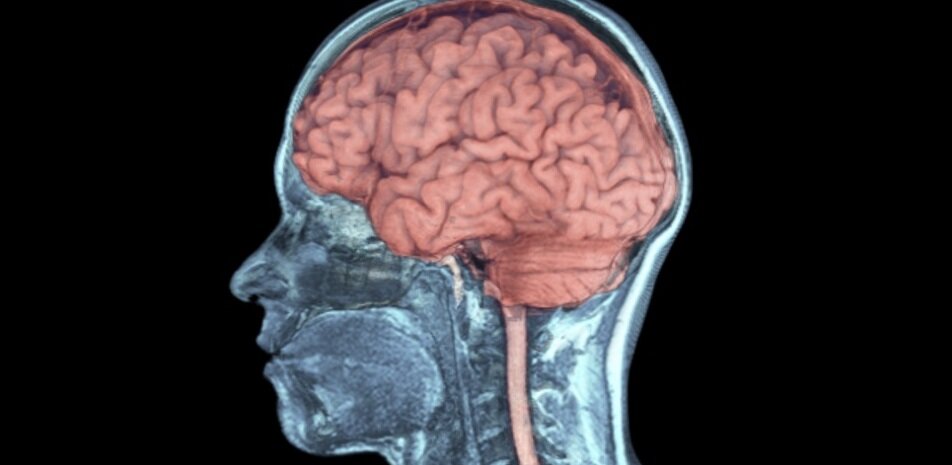

Технология дает ранее недоступные возможности для изучения многих функций мозга на весь изолированный орган. Статья на эту тему была опубликована в журнале Nature. Авторы сообщили о своих экспериментах на заседании комитета по этике Национального института здравоохранения США в апреле 2018 года, однако подробности не разглашаются. Мозг многих млекопитающих очень чувствителен к недостатку кислорода. После того, как кровообращение (перфузия) прекращается в течение нескольких минут, начинается процесс гибели клеток и повреждения нервных волокон. Это, а также образование тромбов в мелких сосудах нарушает исследование функции мозга в динамике ex vivo на изолированном органе. Замораживание и техническое обслуживание позволяют проводить только статические испытания. Ряд наблюдений ставит под сомнение неизбежность гибели нервных клеток в течение нескольких минут или даже часов после прекращения кровообращения и предполагает, что этих ограничений исследований можно избежать. Исследователя

Мозг многих млекопитающих очень чувствителен к недостатку кислорода. После того, как кровообращение (перфузия) прекращается в течение нескольких минут, начинается процесс гибели клеток и повреждения нервных волокон. Это, а также образование тромбов в мелких сосудах нарушает исследование функции мозга в динамике ex vivo на изолированном органе. Замораживание и техническое обслуживание позволяют проводить только статические испытания.

Группа ученых во главе с Ненадом Сестаном из Йельского университета разработала технологически продвинутую систему, которая защищает изолированный мозг от быстрого разрушения, а также решение для питания мозга и специальную хирургическую процедуру для его изоляции. Исследователи показали, что определенные функции мозга могут сохраняться в течение долгого времени после смерти, и существует, по крайней мере, частичный шанс на восстановление.

В мозге, связанном с системой с перфузионным раствором BEx, сохранялась анатомическая и клеточная структура, кровеносные сосуды, обеспечивающие циркуляцию питательного раствора, нейроглифическую функцию, метаболизм тканей и электрическую активность нейронов. Исследователи обнаружили, что поведение клеток и волокон в разных частях мозга было различным.